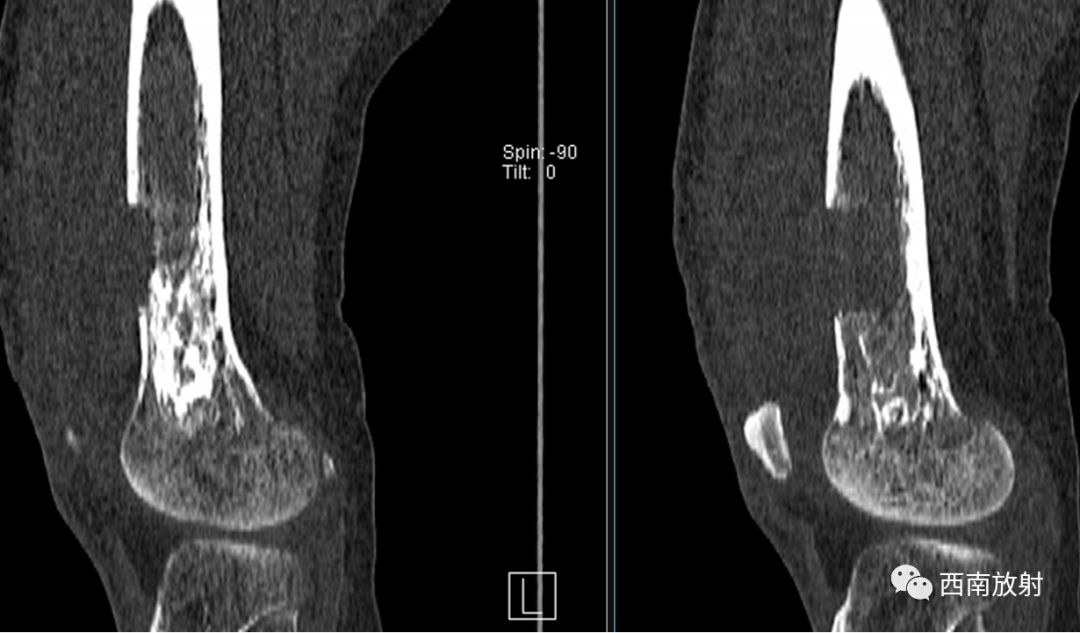

大体病理:右大腿中下段内侧骨膜外见一腔隙,约3X3X4cm,内有较多血凝块,有少许脓液,股骨下段周围有少许脓液,少量疤痕形成,右膝关节内有少许脓液,见有少许脓苔,右骨髓腔未见破坏,骨髓腔内有少许脓液,已被疤痕织包裹。

诊断:慢性骨髓炎,周围软组织脓肿。

CT显示骨破坏、脓肿、死骨及骨膜增生、骨质增生硬化,呈骨小梁密度增高、模糊,髓腔密度增大、狭窄,皮质增厚。MRI显示早期骨髓内广泛分布的斑片异常信号,与邻近正常骨髓信号相比较,T1WI信号减低,T2WI信号增高,脂肪抑制T2WI 或STIR 等序列上病变显示更清楚,骨皮质周围软组织内呈弥漫分布的T1WI低信号及T2WI高信号影,边界模糊。出现骨膜反应,骨皮质不规则破坏,脓肿及死骨形成。

▲骨破坏区及硬化边

▲广泛骨膜增生

▲软组织脓肿